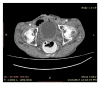

Squamous Cell Carcinoma of Suprapubic Cystostomy Site in a Patient with Long-Term Suprapubic Urinary Catheter

Patients with long-term suprapubic cystostomy can rarely develop squamous cell carcinoma (SCC) of the suprapubic cystostomy tract. In addition to the few reported cases in the literature, this paper reports a case of suprapubic cystostomy SCC in an 88-year-old man without bladder involvement. Vigilance about any abnormal lesion at the site of suprapubic cystostomy is important among health providers and patients for early detection of SCC.